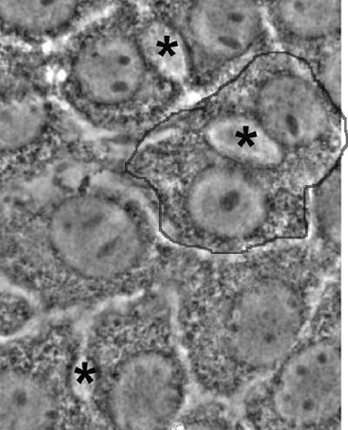

P3 est le chef de file d’une nouvelle famille de chélateurs conçus pour (i) être spécifiques du Cu(I) pour ne pas troubler l’homéostasie du Zn(II) (rapport d’affinités de 1010) ; (ii) cibler les hépatocytes (P3 entre dans différentes lignées cellulaires) ; (iii) s’activer dans le cytoplasme (P3 ne fixe pas le cuivre en absence de réducteur) (Figure 2).

Figure 2 : P3, première molécule remplissant les conditions (i) à (iii).